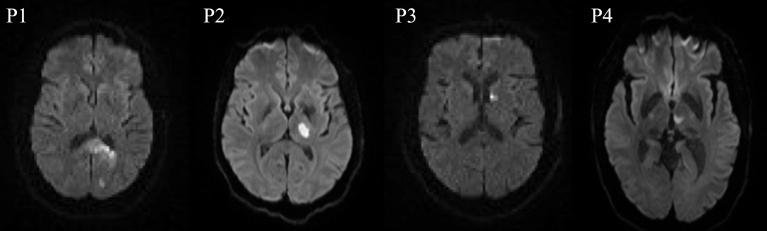

Using task based and resting state functional magnetic resonance imaging (fMRI) and detailed language testing, we longitudinally studied the recovery of the naming network in four participants with PCA stroke with naming deficits at the acute (0 week), sub acute (3-5 weeks), and chronic time point (5-7 months) post stroke. Behavioral and imaging analyses (task related and resting state functional connectivity) were carried out to elucidate longitudinal changes in naming recovery.